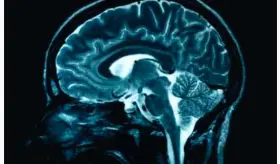

La adherencia al tratamiento es clave para evitar daños cerebrales y facilitar la recuperación en la condición.